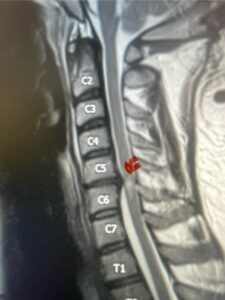

A 37-year-old male police officer complained of a one-month history of difficulty with his balance and leg weakness. He complained of achiness in his legs. He also complained of bilateral arm weakness and numbness of his hands. He was also having difficulty writing due to the weakness. Patient had an MRI of the cervical spine which demonstrated a disc/osteophyte at C56 causing spinal cord compression and concurrent myelomalacia (Fig. 3). Patient underwent an anterior cervical discectomy with a cage and plate (Fig. 4). He tolerated the procedure well with improved numbness and weakness. This is a young person with fairly extensive myelomalacia and a fairly rapid development of symptoms. For this it was felt surgery was indicated. How he will do will depend on how much of his symptoms was caused by the compressive component or intrinsic damage to the spinal cord. As a rule, patients generally improve to some extent quickly; but their recovery of their spinal cord function can sometimes take up to 2 years to realize the extent of their improvement. Patients have to be patient with themselves in terms of their expected recovery.

Fig 4: Sagittal T2-weighted cervical MRI demonstrating a significant disc osteophyte complex causing spinal cord compression at C 5 6 with extensive myelomalacia (red arrow)